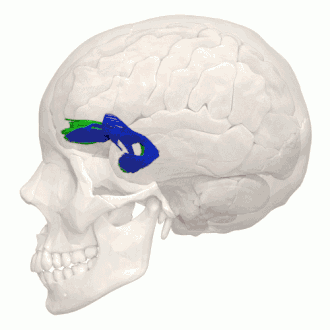

![]() Tractography of the uncinate fasciculus. | |

Tractography showing uncinate fasciculus. -

Animation of tractography data. Blue is the left, green is the right.